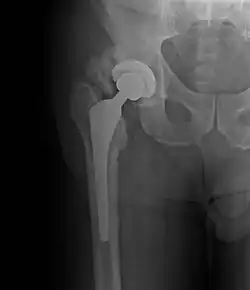

Heterotopic ossification around the hip joint in a patient who has undergone hip arthroplasty |

Heterotopic ossification (HO) is the process by which bone tissue forms outside of the skeleton in muscles and soft tissue.[1]

Heterotopic ossification of varying severity can be caused by surgery or trauma to the hips and legs. About every third patient who has total hip arthroplasty (joint replacement) or a severe fracture of the long bones of the lower leg will develop heterotopic ossification, but is uncommonly symptomatic. Between 50% and 90% of patients who developed heterotopic ossification following a previous hip arthroplasty will develop additional heterotopic ossification.